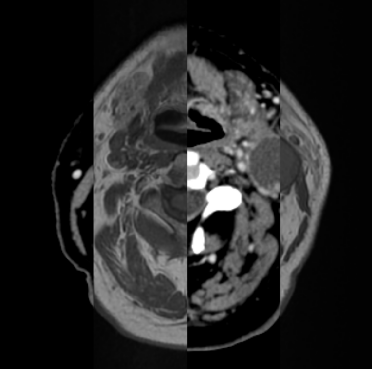

Organ at risk (OAR) segmentation is a critical process in radiotherapy treatment planning such as head and neck tumors. Nevertheless, in clinical practice, radiation oncologists predominantly perform OAR segmentations manually on CT scans. This manual process is highly time-consuming and expensive, limiting the number of patients who can receive timely radiotherapy. Additionally, CT scans offer lower soft-tissue contrast compared to MRI. Despite MRI providing superior soft-tissue visualization, its time-consuming nature makes it infeasible for real-time treatment planning. To address these challenges, we propose a method called SegReg, which utilizes Elastic Symmetric Normalization for registering MRI to perform OAR segmentation. SegReg outperforms the CT-only baseline by 16.78% in mDSC and 18.77% in mIoU, showing that it effectively combines the geometric accuracy of CT with the superior soft-tissue contrast of MRI, making accurate automated OAR segmentation for clinical practice become possible. See project website https://steve-zeyu-zhang.github.io/SegReg